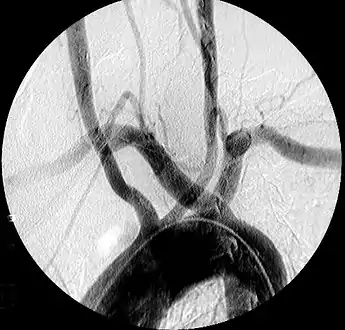

![]() | |

| Aberrant subclavian artery on MR angiography. | |